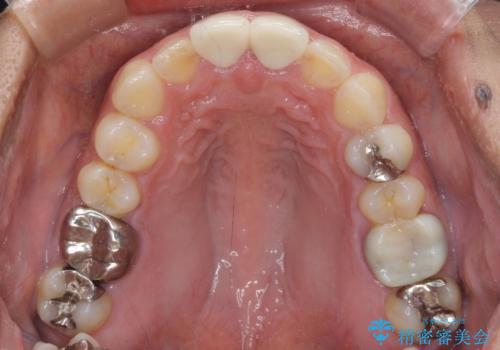

治療を提供する側からすると、歯が短すぎるように思えますが、患者様としては長年気になっていた形態が改善され、大変満足していただきました。